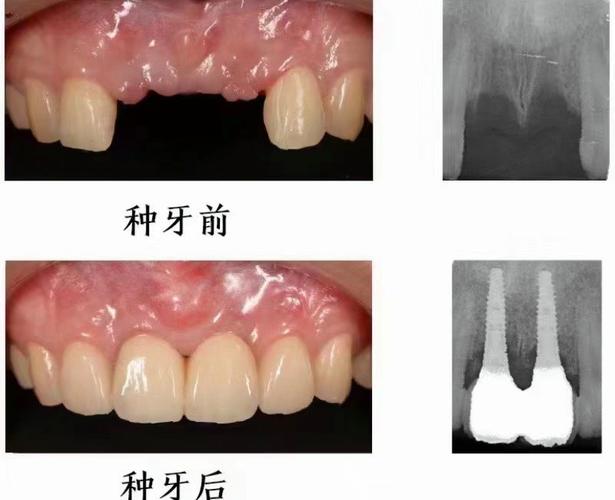

(图片来源网络,侵删)